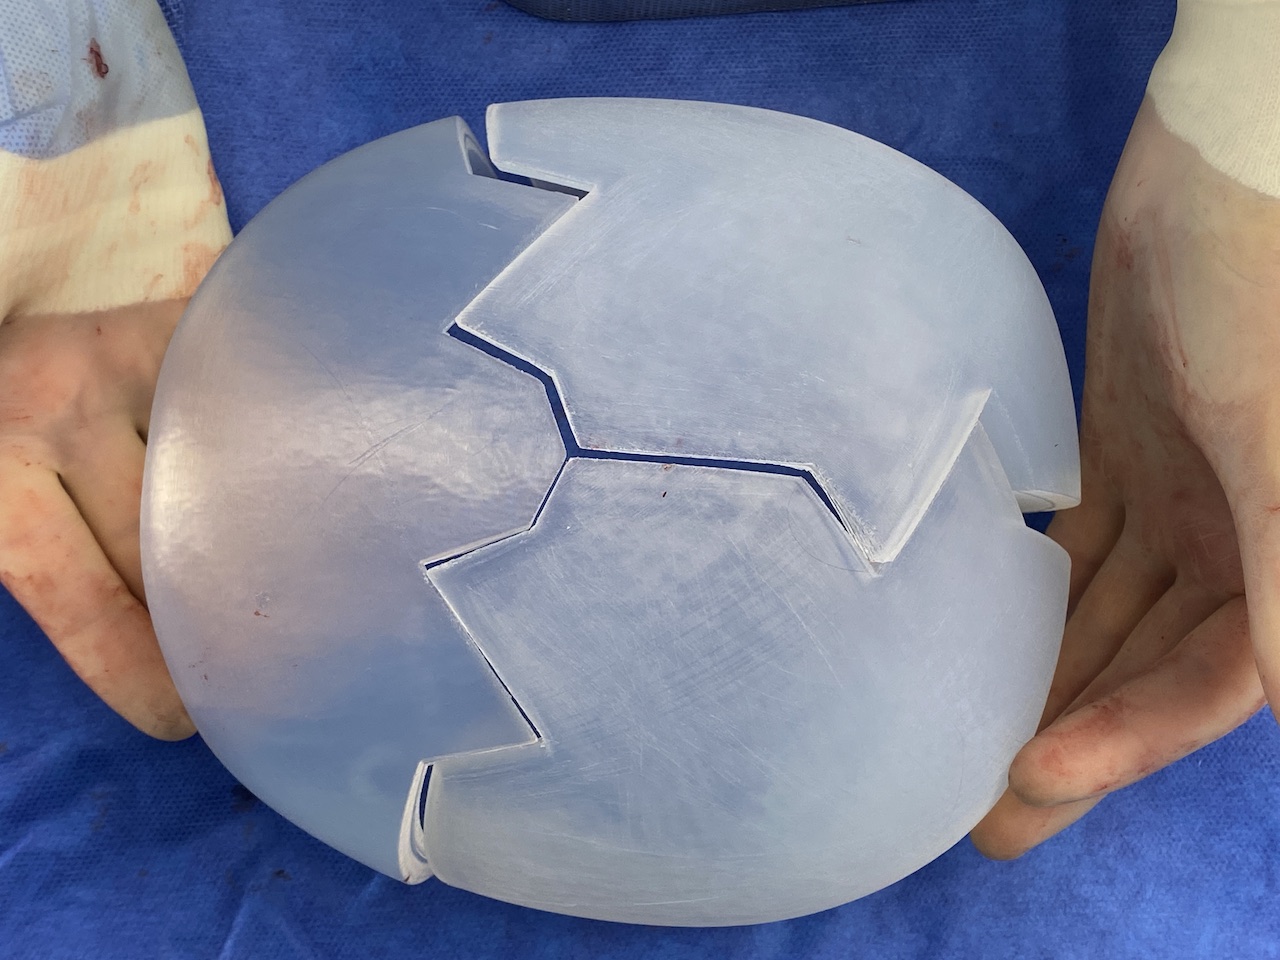

Desire for large overall skull augmentation procedure. Two piece custom skull implant designed with 250ccs volume.

1st stage scalp expander placed and inflated to 225ccs. 2nd stage two piece skull implant placed 4 months later.

Desire for large overall skull augmentation procedure. Two piece custom skull implant designed with 250ccs volume.

1st stage scalp expander placed and inflated to 225ccs. 2nd stage two piece skull implant placed 4 months later.